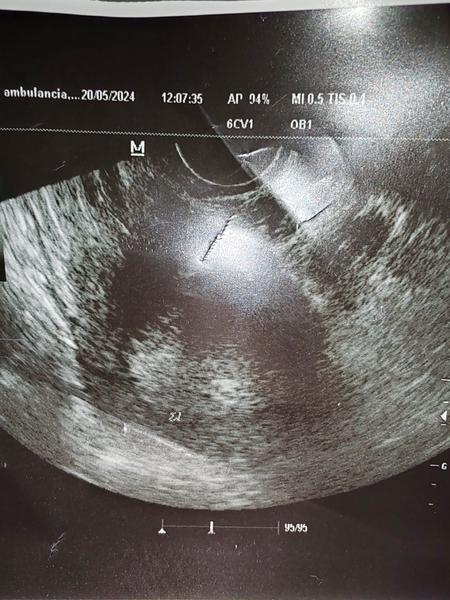

@mirka17 Tu je lepšia fotka ta prvá bola taka na rýchlo no je to jedna a tá istá.

Dobrý deň tak dneska som bola povedala mi že je to strašne maličké že ak príde menštruácia tak to môže zobrať 😔 ja na tom ultrazvuku skoro nič nevidím. Povedala mi že ona tam vidí len vačok. Dneska podľa menštruácie vychádza že by som mala byť v 6.Týždni. V piatok idem znovu. Vôbec neviem čo si mám o tom myslieť. Je to ťažké pre mňa. Ďakujem Vám všetkým za rady a odpovede.

@vevericaxxl vacok je zaklad, uvidi sa v piatok ci bude aj nieco viac. Datum poslednej menstruacie je len orientacny, ovulacia mohla nastat neskor. To cakanie je mucive ale je to dan za to ze to chceme vediet tak skoro. Pokracujem v silnom drzani palcov ❤️